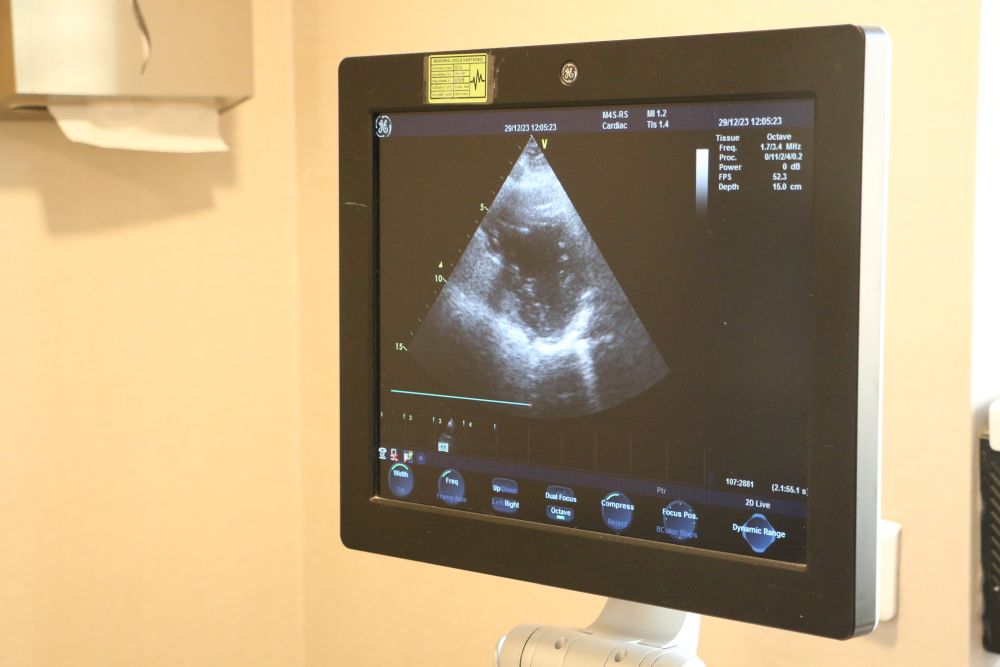

Diyarbakır’da Dicle Memorial Hastanesi’nde Uzman Doktor Hüseyin Akçalı, geçirilmiş kalp krizi sonrası özellikle kalp kapak hastalığını ortaya çıkabileceğini söyledi.

Kalp kapaklarının vücutta 4 tane bulunan, kan akışını sağlayan ve kan akışına yön veren kapaklar olduğu bilgisini veren Dr. Akçalı,